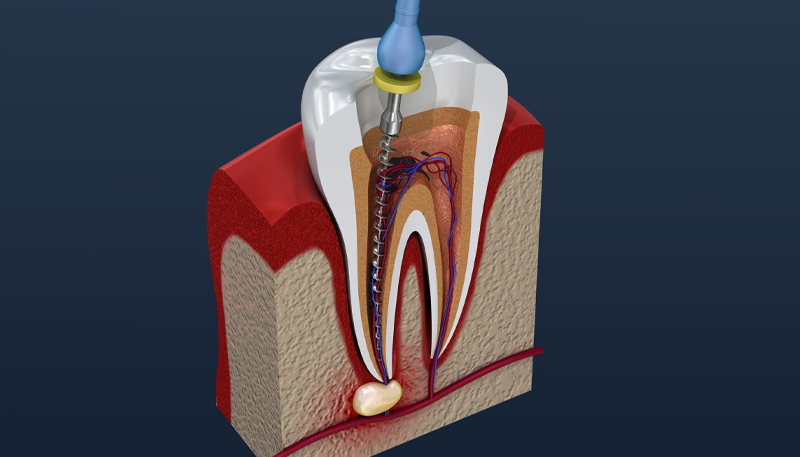

根管治療

| マイクロスコープ 精密根管治療 (1根管) |

前歯 44,000円(税込) 小臼歯 55,000円(税込) 大臼歯 66,000円(税込) |

|---|---|

| VPT | 22,000円 (税込) |

| 歯根端切除 | 55,000円 (税込) |

| コア | 5,500円 (税込) |

| CT | 16,500円 (税込) |